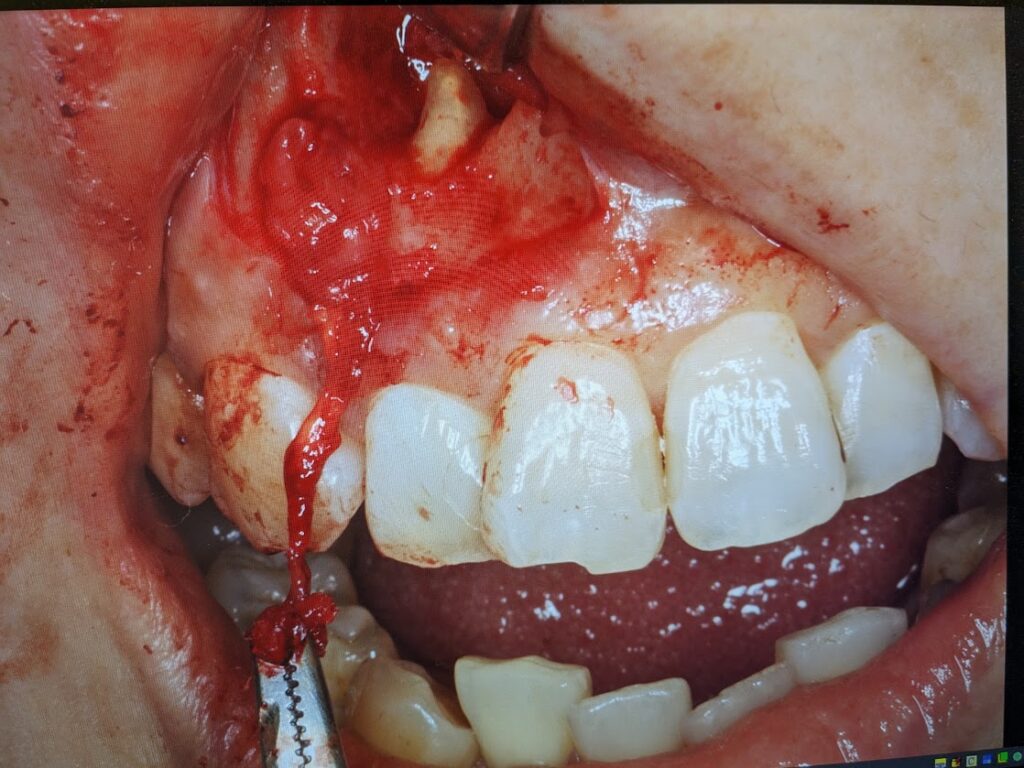

手術直前の写真です

歯肉退縮を避けるように切開線を設定して歯肉粘膜骨膜弁を剥離していきますと骨膜と癒着した嚢胞壁が認められました。骨膜と癒着した嚢胞壁をできるだけ丁寧に剥離していきます。マイクロスコープを使用しますと裸眼で手術するより骨膜と嚢胞壁の堺目が良く分かります。

骨膜と分離した嚢胞を明示します。今度は骨内にある嚢胞をできるだけ一塊に摘出していきます。